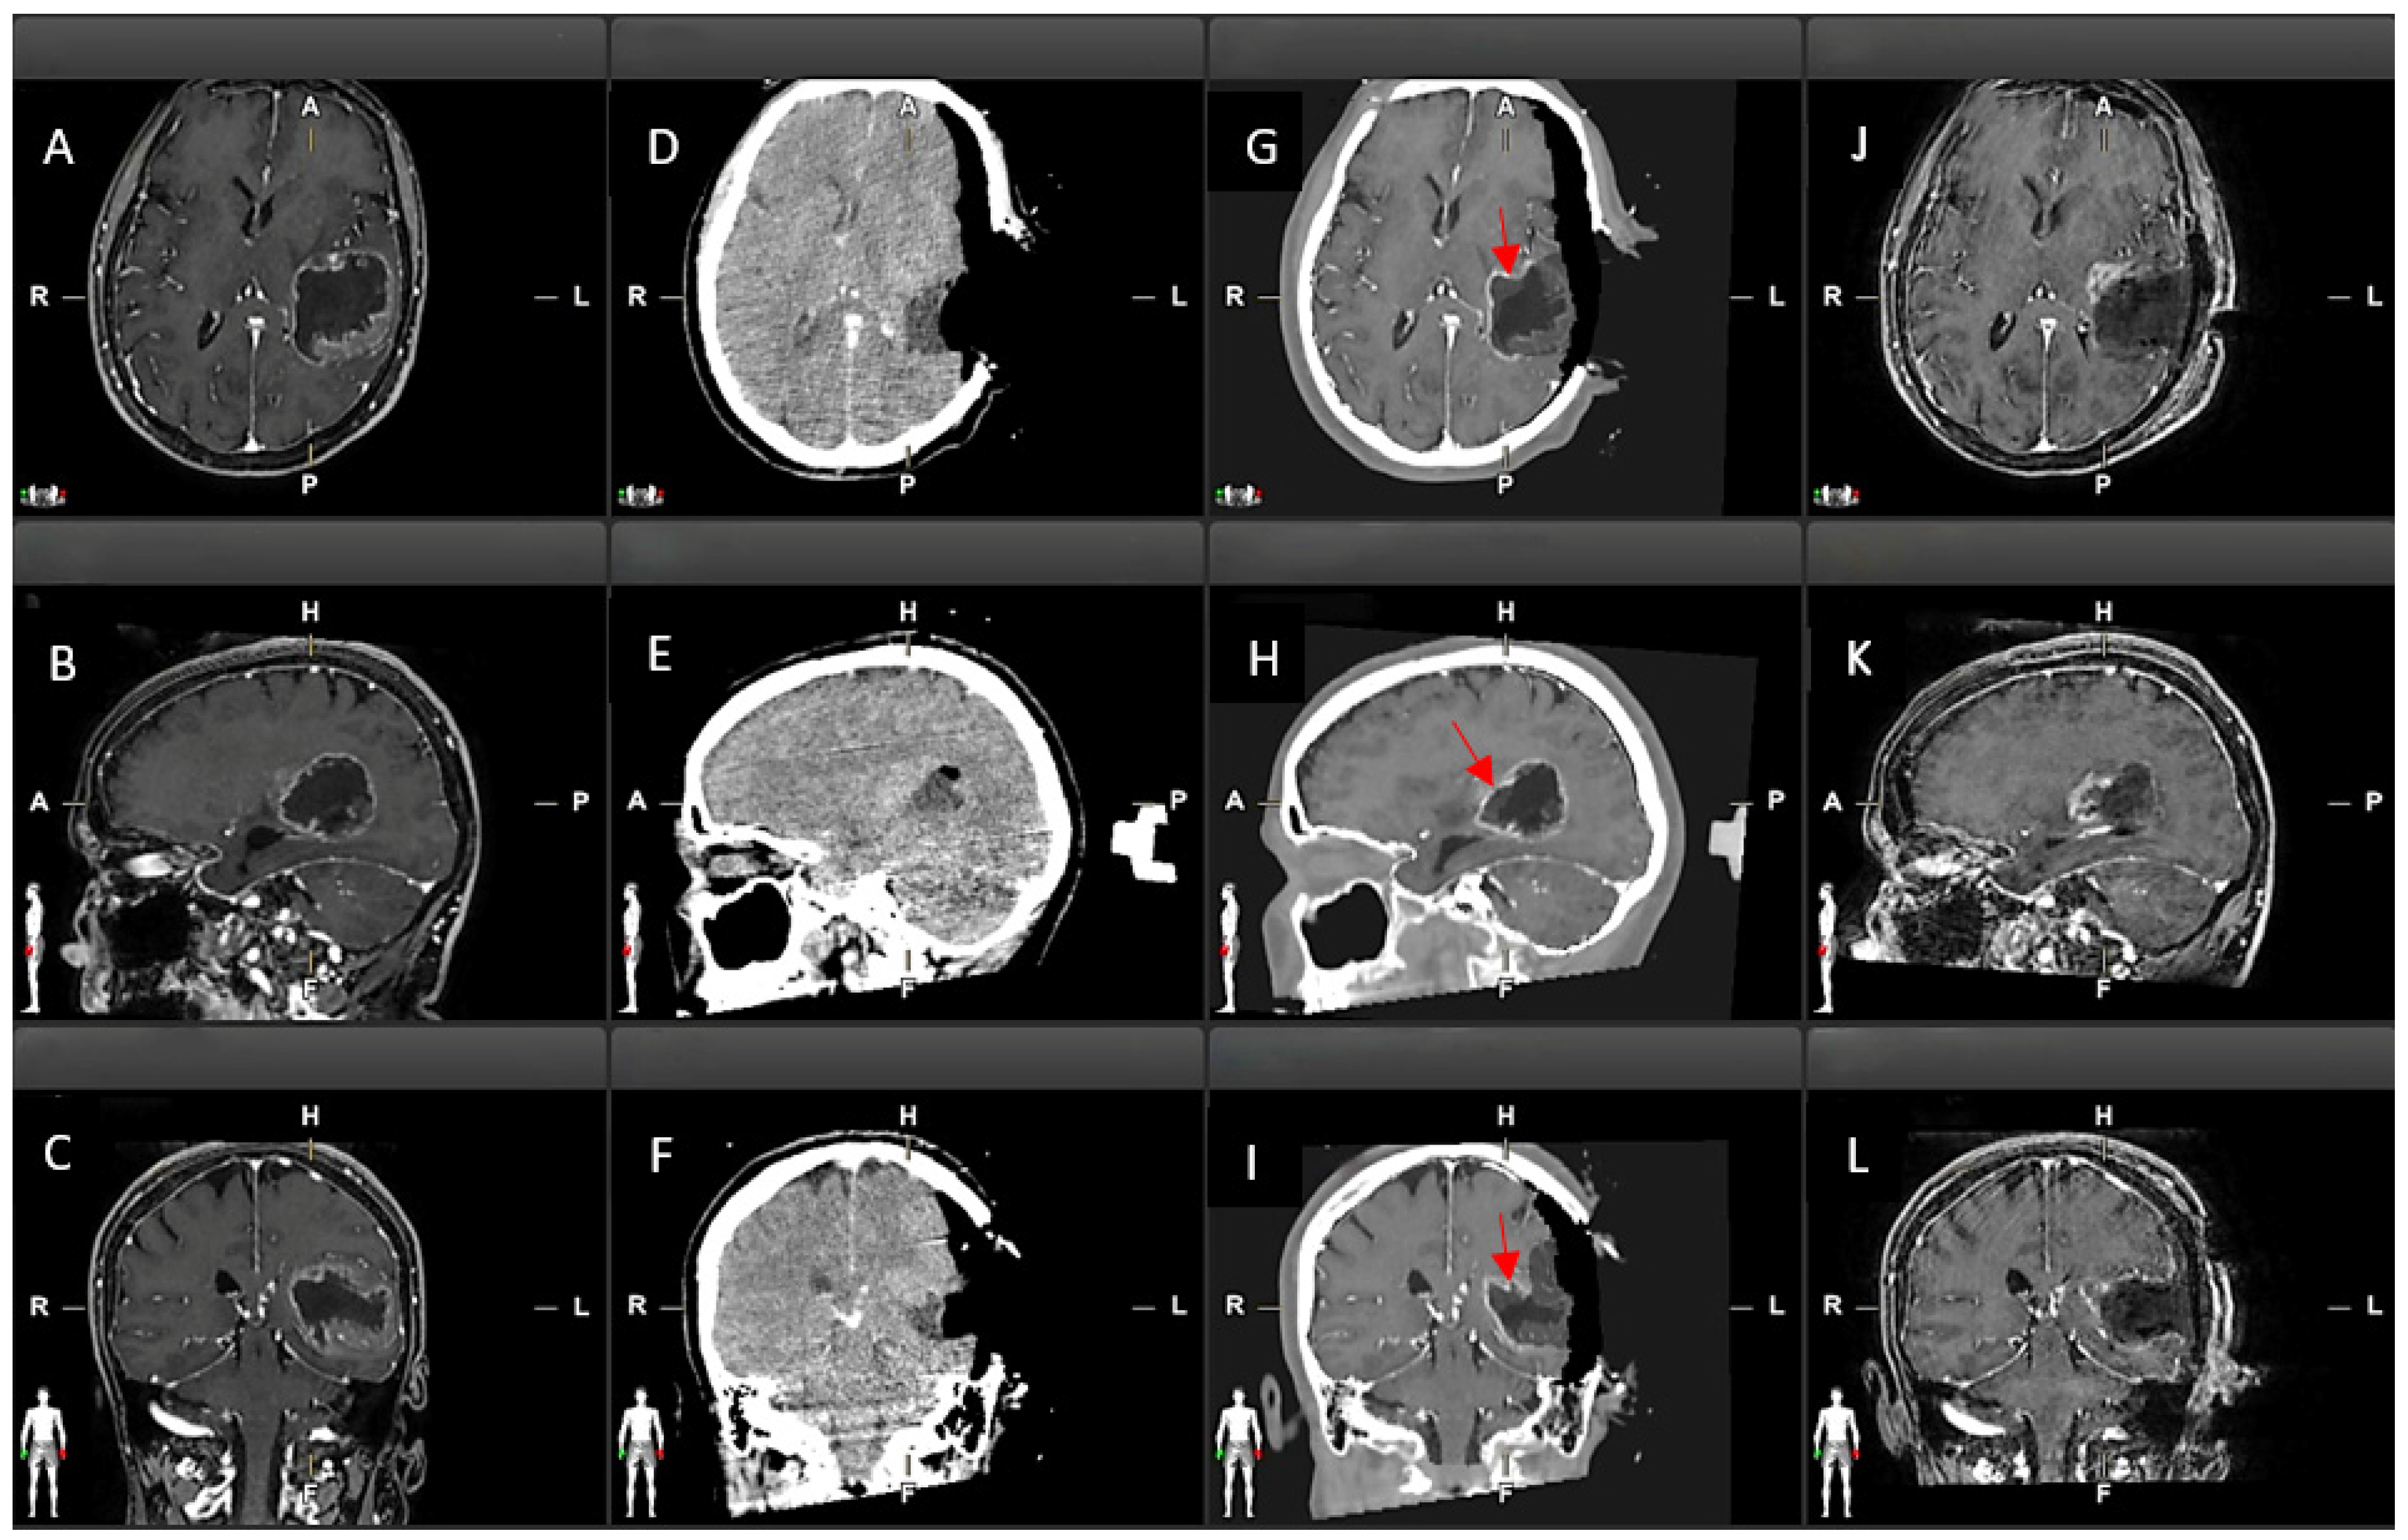

3.1. Residual Tumour

3.3. Qualitative Evaluation

| TC | Virtual iMRI | |

|---|---|---|

| FP | 0 | 27 |

| FN | 13 | 0 |

| TP | 17 | 26 |

| TN | 50 | 27 |

| SENSITIVITY | 0.56 | 1 |

| SPECIFICITY | 1 | 0.5 |

| PPV | 1 | 0.49 |

| NPV | 0.79 | 1 |